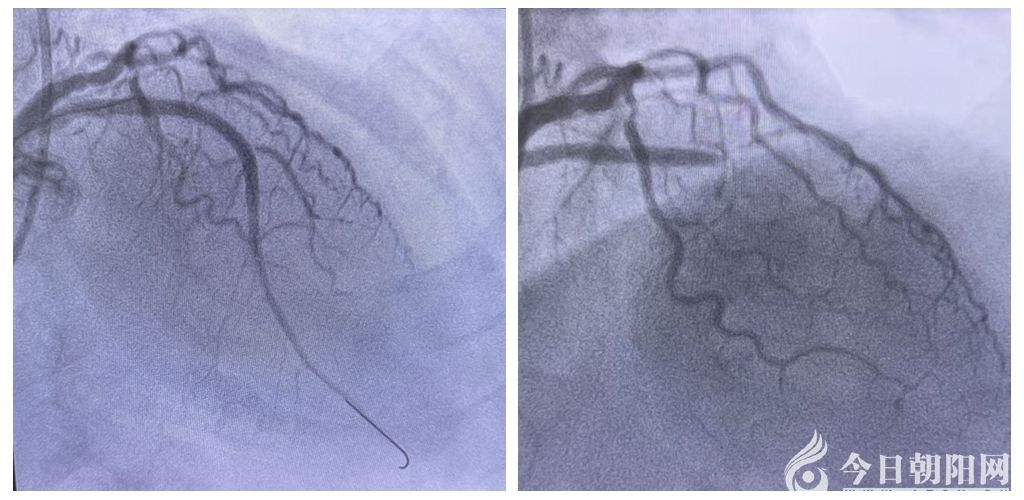

確診并接到轉(zhuǎn)診通知后,醫(yī)院胸痛中心團隊即刻啟動應急機制,第一時間開通120綠色通道,讓救護車直接將患者送往導管室準備手術。與此同時,醫(yī)院心內(nèi)科胸痛中心介入團隊嚴陣以待,對患者實施冠脈介入手術。治療團隊爭分奪秒,為患者完成血管造影、球囊擴張及支架植入手術,成功開通了閉塞血管?;颊甙Y狀立即得到緩解,從基層衛(wèi)生院檢查到醫(yī)院心內(nèi)科救治,全程實現(xiàn)無縫銜接。術后,患者生命體征平穩(wěn),安全返回病房,目前繼續(xù)在心內(nèi)科病房接受后續(xù)治療?;鶎俞t(yī)生與上級醫(yī)院醫(yī)護人員攜手合作,成功完成這場與死神較量的“接力賽”,贏得了患者和家屬的肯定與感謝。